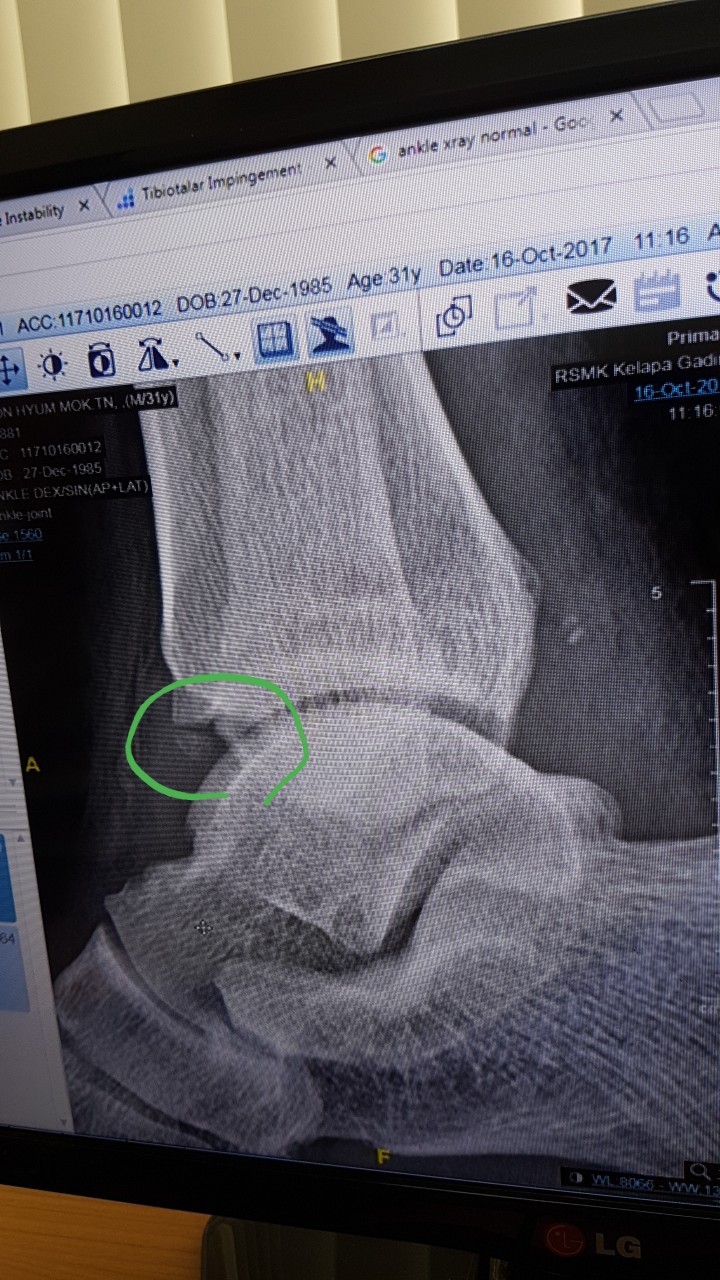

안녕하세요저는 인도네시아에서 현재 근무를 하고 있습니다.다름이아니라 2주전에 운전을 오래하고 골프를 치고 난 후 그다음부터 오른 발목이 시큰시큰 아프더니 결국 붓기가 올라 아직도 붓기가 빠지지 않고 있습니다.그리하여 한의원도 가보고 진통소염제 등 약도 먹어보다 어제 xray를 찍고 검사를 했는데 엑스레이 결과를 보고 Tibiotalar impingement 라고 합니다.수술을 해야한다는데 사실 외국이라 의학용어를 정확하게 몰라 다시한번 여쭙고자 합니다.필요시 한국에서 검사하고 수술할생각도 있어 한번 확인 부탁 드립니다아래의 사진에 동그라미 친부분을 제거해야한다는데 부탁드립니다어떤 수술을 해야하며 얼마나 걸릴까요 ? 제가 외국에서 근무를 해서 휴가기간을 정해야합니다.빠른답변 기다리겠습니다. ㅇ

사용자 등록 이미지 |

286.0K

|

501 Download(s)